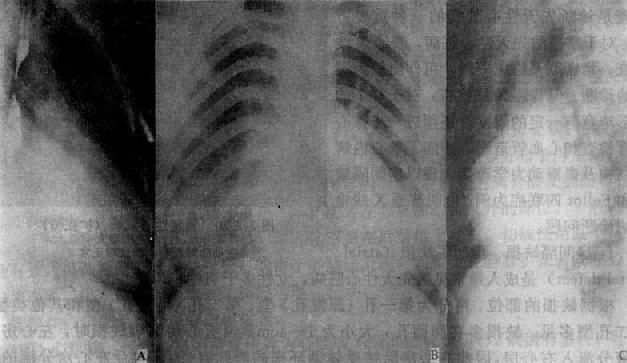

X线表现,当缺损小,分流量少时,心大小和形状正常或改变不明显。缺损较大即有以下改变(图3-2-21):①心呈二尖瓣型,常有中度增大;②右心房及右心室增大,尤以右心房显著增大为心房间隔缺损的主要特征性改变;③肺动脉段突出,搏动增强,肺门血管扩张,常有“肺门舞蹈”现象;④左心房一般不增大,第二孔型左心室和主动脉球变小,而第一孔型左心室增大;⑤肺充血,后期可出现肺动脉高压。

图3-2-21 房间隔缺损

右前斜位:右心室增大,肺动脉段突出,心前间隙变窄,无左心房增大后前位:心增大,呈二尖瓣型,右心房及右心室增大,肺动脉段突出,肺纹理增强左前斜位:右心房及右心室增大,左心室被增大的右心室推向后